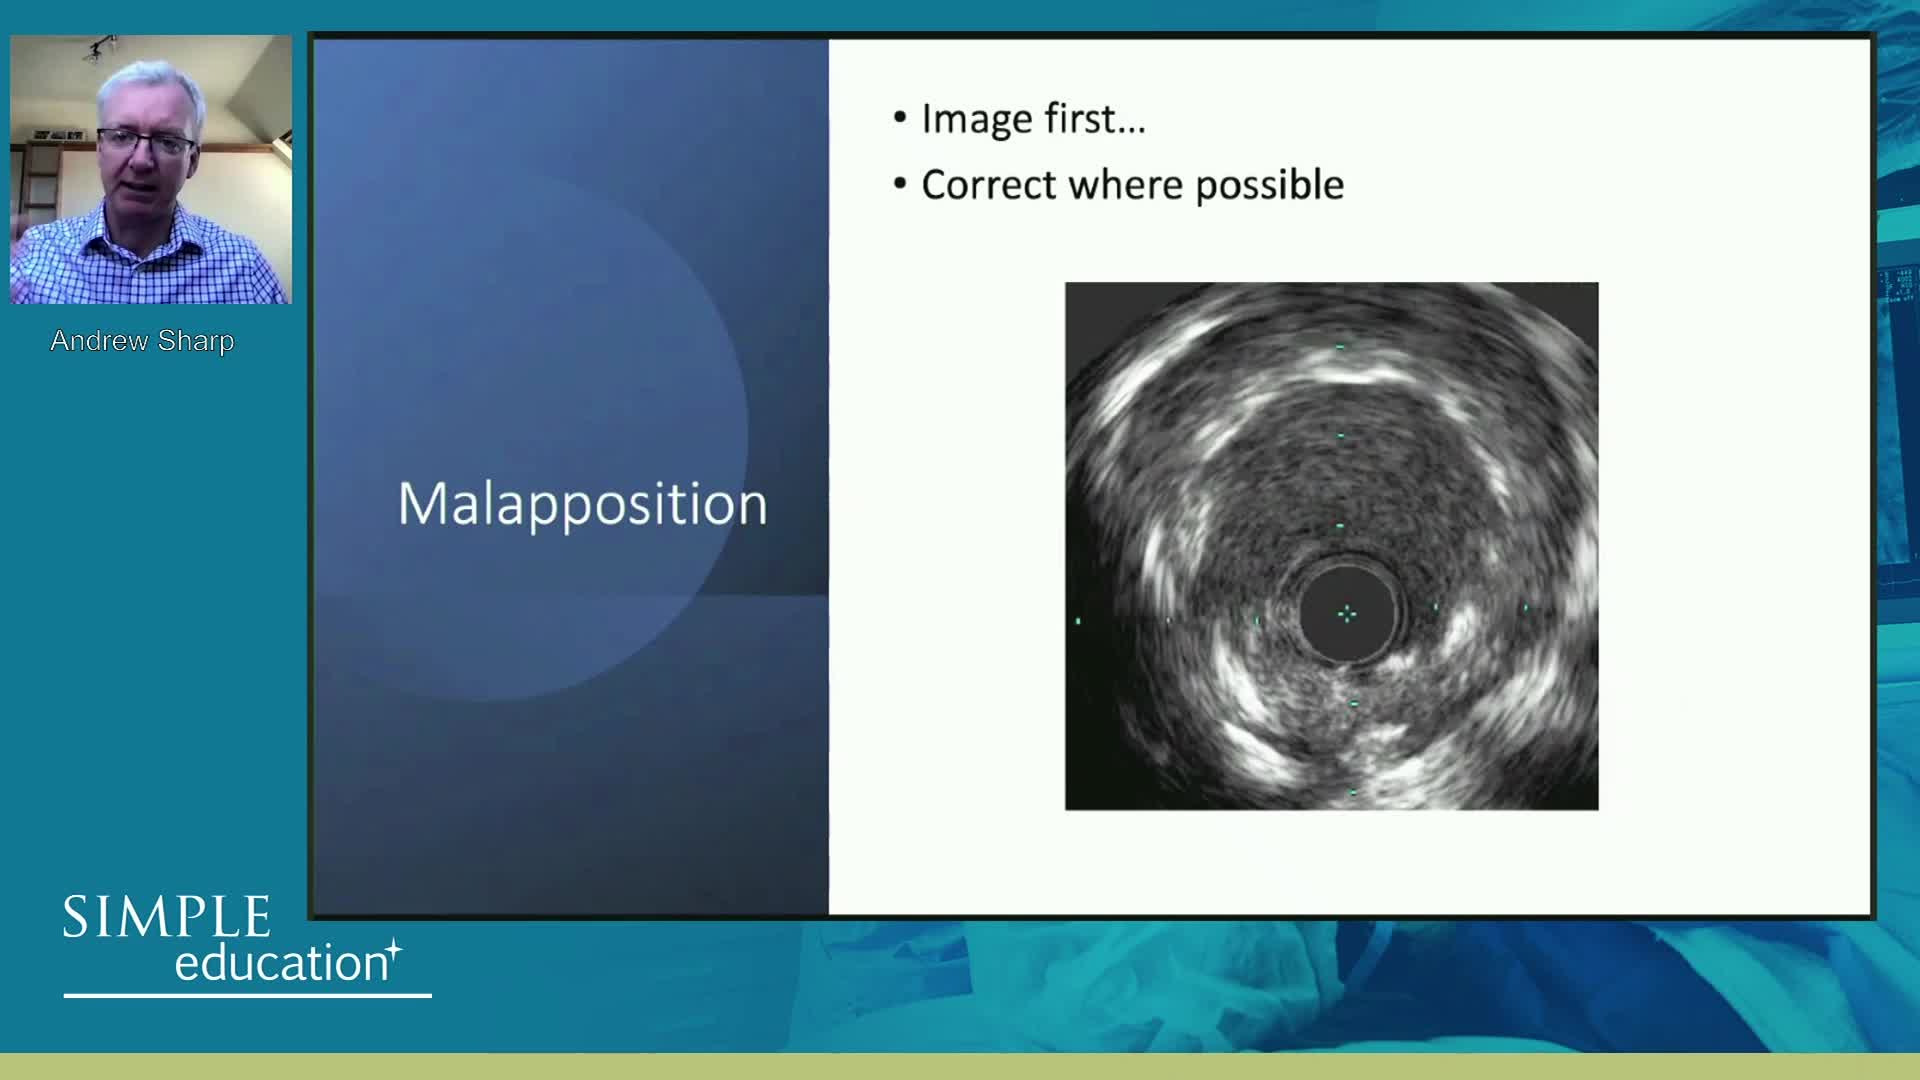

How to perform good co-registration measurements using iFR and IVUS - Prof Carlo Di Mario

Using SyncVision Co-registration to distinguish between focal and diffuse coronary disease. - Prof Giuseppe Tarantini

Essential steps for physiology-based PCI planning and guidance - Dr Allen Jeremias